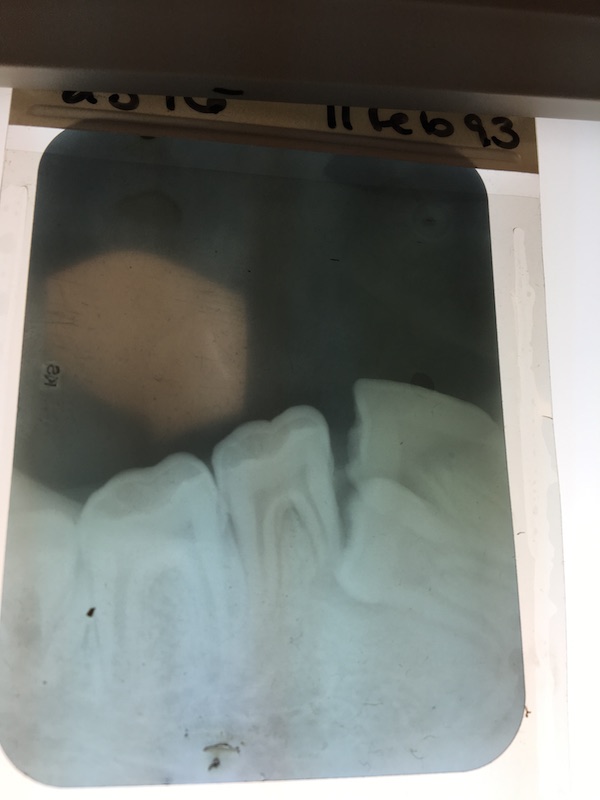

Tommy Orangutann, young adult, impacted mandibular premolar case

Radiograph of canine

Radiograph of fistula

Radiograph of bone repair three (?) months post op

Canine endo follow up